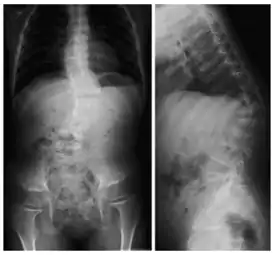

![]() Рентгеновский снимок позвоночника пациента с кифосколиозом. На проекциях хорошо видно искривление позвоночного столба вбок (сколиоз) и выпуклостью назад (увеличенный кифоз) | |